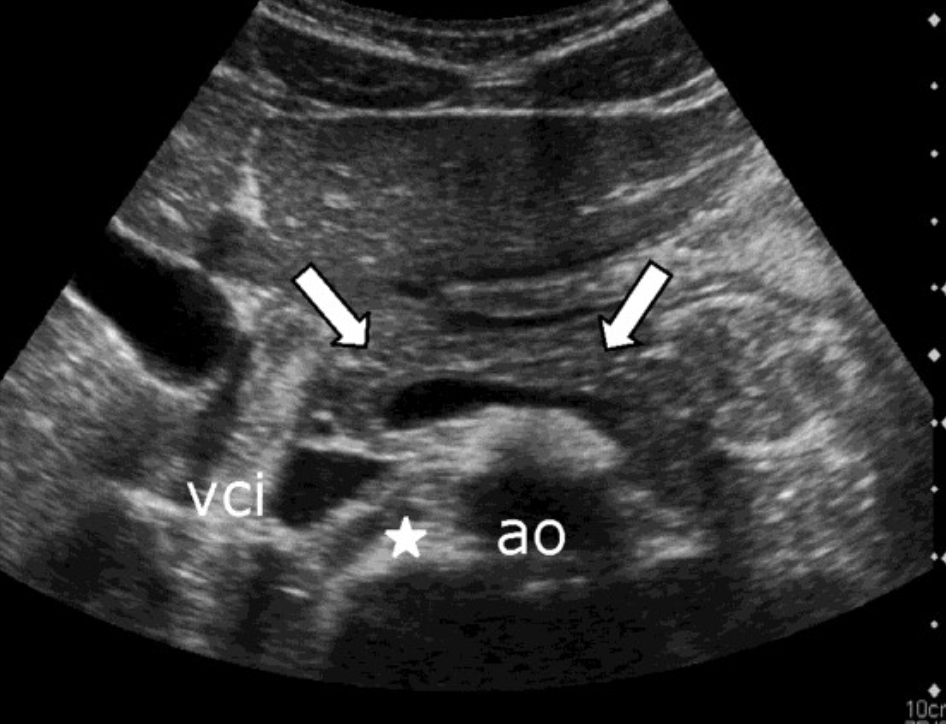

Aortic Dissection → intimal wall tears and allows blood flow between layers

2D US presentation: thin echogenic linear membrane fluttering in lumen creating a true and false lumen

color doppler: fill in both channels → pw shows regular flow in true and weak/no flow in false; asymmetrical kidney perfusion

DDX: AAA (focal dilation, no intimal flap)

AAA (Abdominal Aortic Aneurysm) → focal dilation of aorta

2D US presentation: focally dilated AO (3 cm or greater), mural hypoechoic thrombus, wall calcifications, usually located infrarenal, can be fusiform or saccular

color doppler: turbulent helical flow